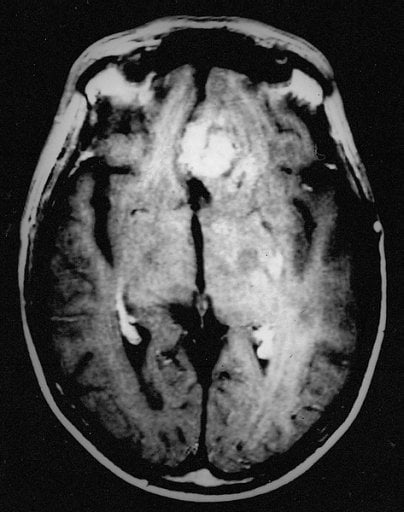

Image Source: The brain scan of a patient with recurrent glioblastoma is available in the public domain.